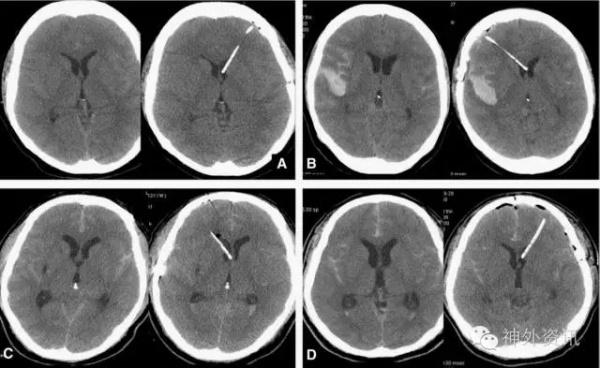

经终板三脑室切开引流置管术(见图4、图5、图6、图7).

图4. 经终板三脑室切开引流置管术。

图5. 经终板三脑室切开引流置管术。

图6. 经终板三脑室切开引流置管术。

图7. 经终板三脑室切开引流置管术。

经额下终板入路是颅咽管瘤的常用入路;而在动脉瘤手术中,亦可以通过打开终板,进一步的释放脑脊液降低颅内压,以达到Slack Brain,减少额颞叶的牵拉。有学者提出,破裂动脉瘤术中打开终板,不仅可有效降低颅压,还可降低术后交通性脑积水的发生率,但此观点在某些单中心回顾性研究中并未得到证实。

对于H&H分级、Fisher分级较高的SAH病例,术中留置脑室引流管有利于术后的脑压下降及脑压监测,血性脑脊液的持续引流有利于减少血管痉挛及交通性脑积水的发生。

相比于常规Paine’s点穿刺侧脑室留置脑室引流管,经终板留置三脑室引流管优势劣势均十分明显。

优点没有额外的脑实质损伤;

不会出现穿刺道血肿;

操作均在显微镜下直视进行,无穿刺失败率。

引流管较脑室引流管细,容易出现引流管堵塞;

对于指向下的前交通动脉瘤,打开终板时容易导致动脉瘤破裂;

“Red,Angry,Swollen Brain”,此种脑压非常高的情况,仅通过释放颅底池脑脊液,很难暴露终板,此种情况仍需行Paine’s点穿刺。